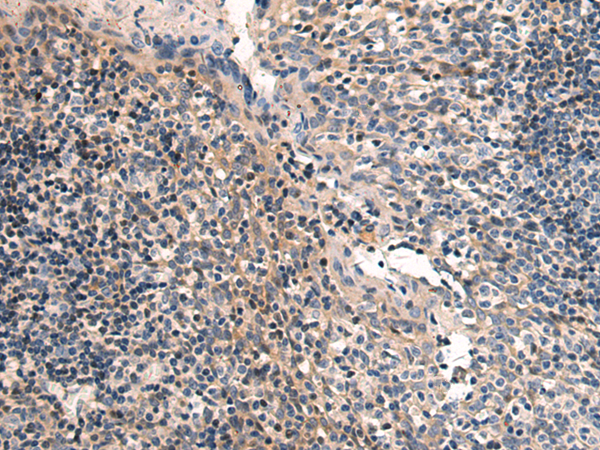

IHC positive control: |

Human tonsil |

IHC Recommend dilution: |

50-100 |